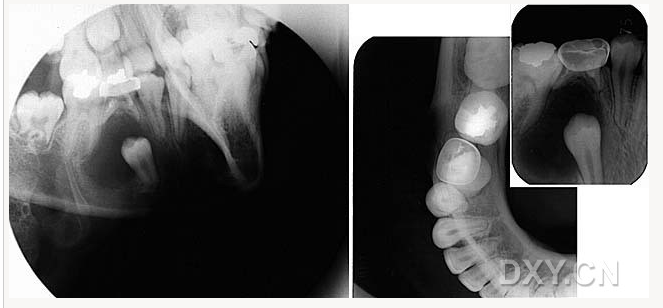

涎石病

球狀上頜囊腫

含牙囊腫

球狀上頜囊腫    含牙囊腫